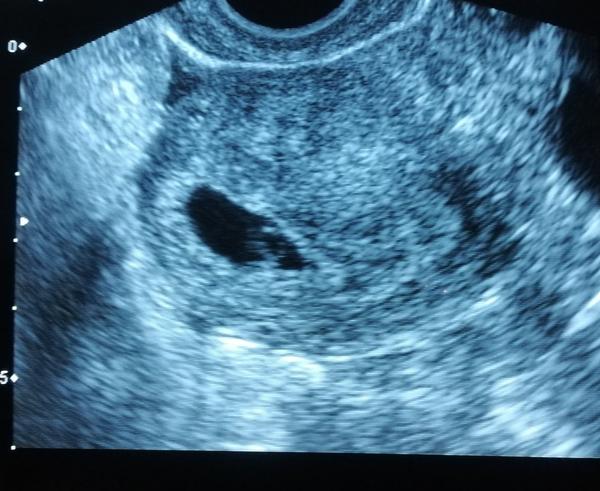

Ahoj holky, jsem dnes 5+2 TT. Na vaginálním utz.byl vidět jenom gestační váček. Mám přít za 14 dní. Jsem vyplašená. Nevím co si o tom mám myslet..😌😌

Nemáte někdo prosím zkušenost..? Děkuji moc za rady, a všem přeji pohodové těhotenství.